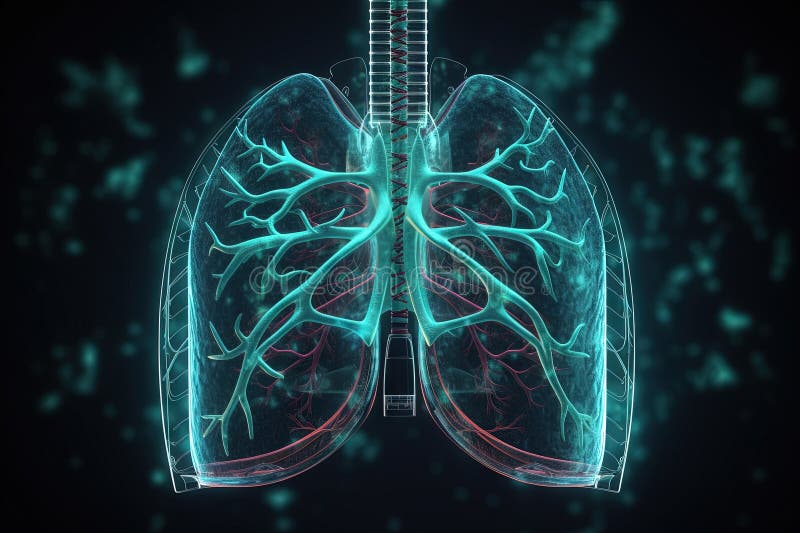

Artificial implant science concept with technological AI lungs on the circuit board. Generated AI AI generated